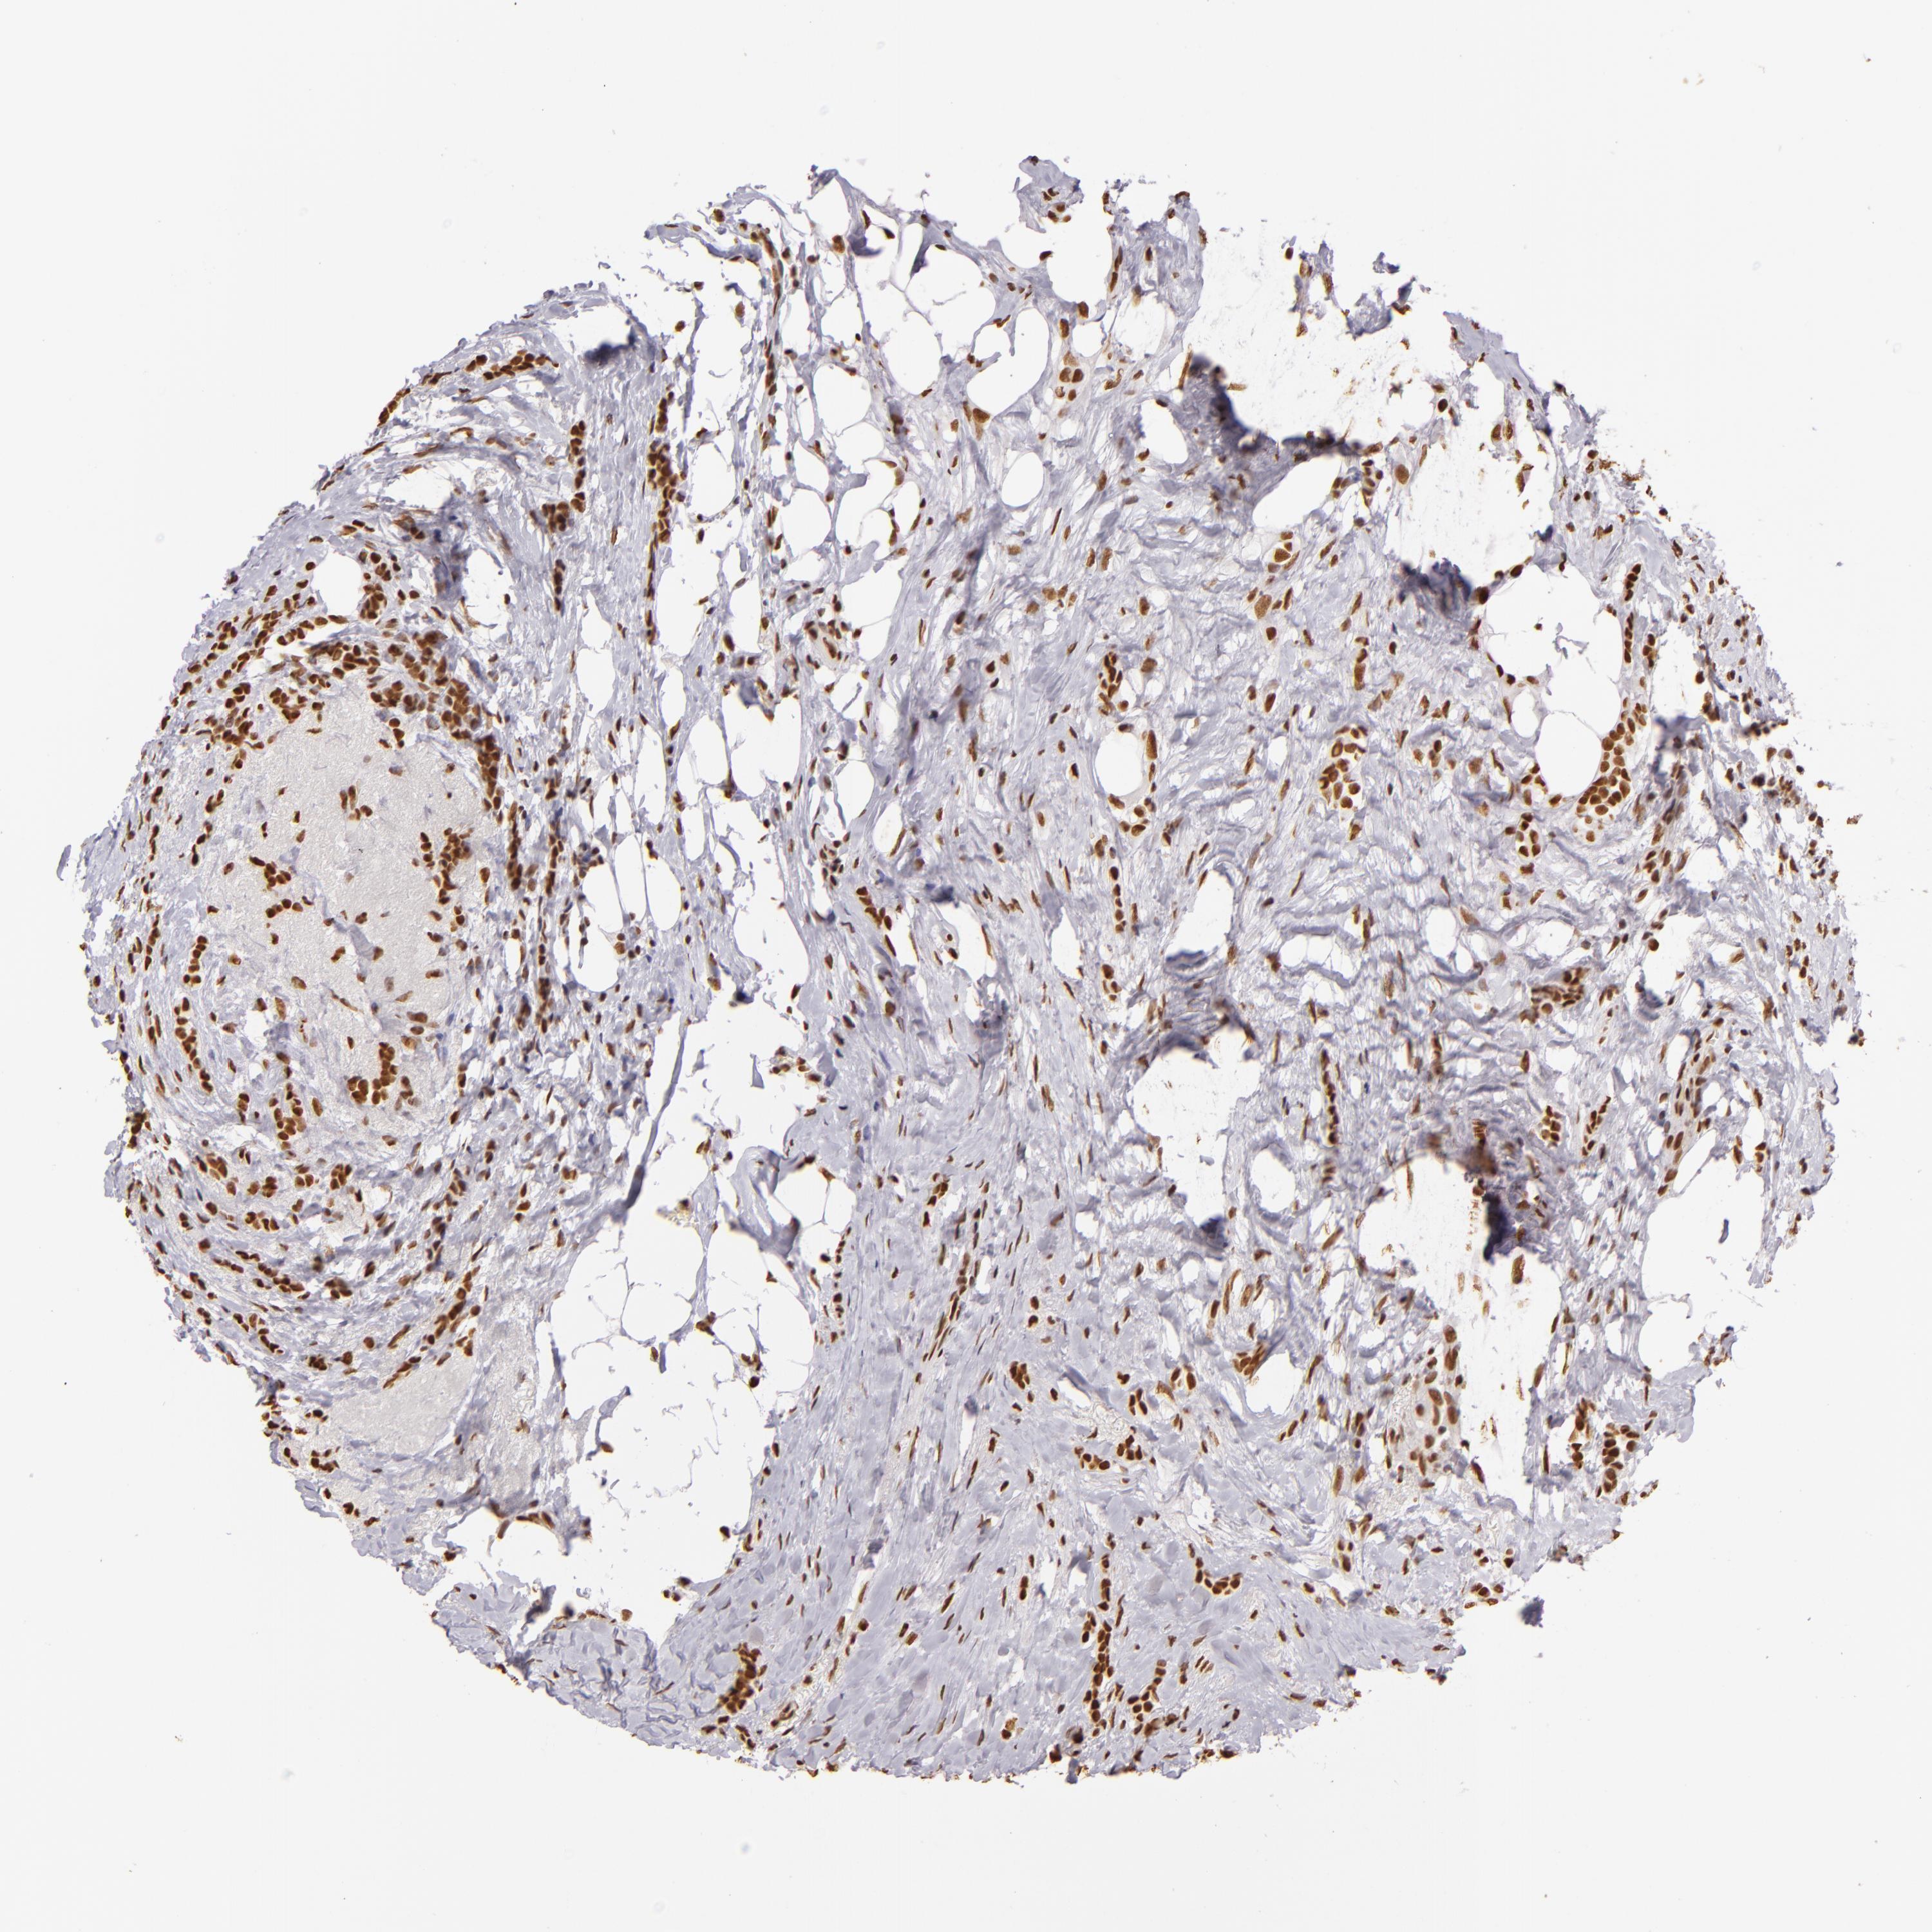

CANCER BREAST CANCER Show tissue menu

BRCA TCGA BRCA VALIDATION PROTEIN EXPRESSION